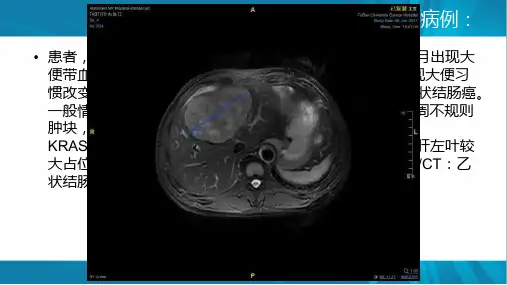

中国结直肠癌肝转移诊断和综合治疗指南(2020版)中国结直肠癌肝转移诊断和综合治疗指南(2020版)单击输⼊您的封⾯副标题1结直肠癌肝转移的诊断与随访结直肠癌肝转移的定义:同时性肝转移是指结直肠癌确诊前或确诊时发现的肝转移;⽽结直肠癌根治术后发⽣的肝转移称为异时性肝转移。

《指南》分别从下⾯两个⽅⾯进⾏阐述01“结直肠癌确诊时合并肝转移”02“结直肠癌根治术后发⽣肝转移”⼀、结直肠癌肝转移的诊断与随访:结直肠癌确诊时肝转移的诊断常规对已确诊结直肠癌的患者,除⾎清癌胚抗原(CEA)、糖类抗原19-9(CA19-9)等肿瘤标志物检查、病理分期评估外,应常规进⾏肝脏超声和腹部增强CT等影像检查以筛查及诊断肝脏转移瘤。

对于超声或CT影像⾼度怀疑但不能确诊的患者,可⾏⾎清甲胎蛋⽩(AFP)、肝脏超声造影和肝脏MRI平扫及增强检查(1a类证据,A级推荐),需要时可⾏肝脏细胞特异性造影剂增强MRI检查。